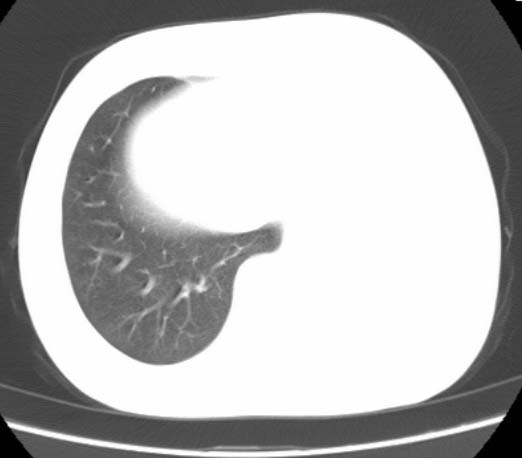

标题: CT25648:求教:是肺发育不全还是结核?

女  20岁。一月前咳血,诊“肺结核”抗痨治疗一月后,咳血停止,现复查。病人精神好。前后ct片对比未见明显变化。既往体检“正常”

1)考虑左肺结核并肺不张、支气管扩张。2)纵隔疝。

考虑左肺结核,左肺毁损,纵膈左偏,既往体检正常不可靠,tb一个月也不会这个样子的,有钙化,应该病程较长,冰冻三尺非一日之寒!

左肺发育不全。